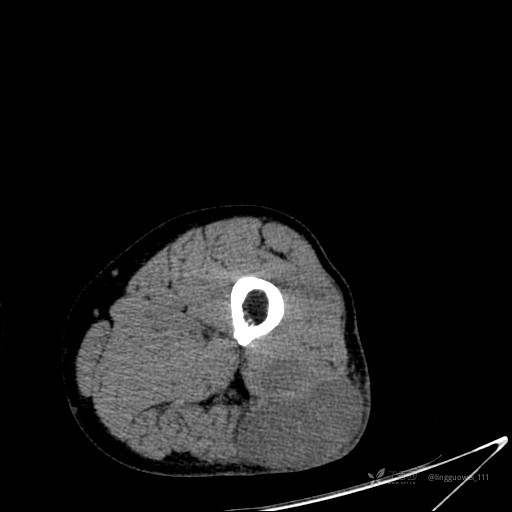

患者性别:男,85岁。发现大腿软组织肿块1年,增大3月,良性还是恶性?只有CT,能诊断正确吗?

平扫